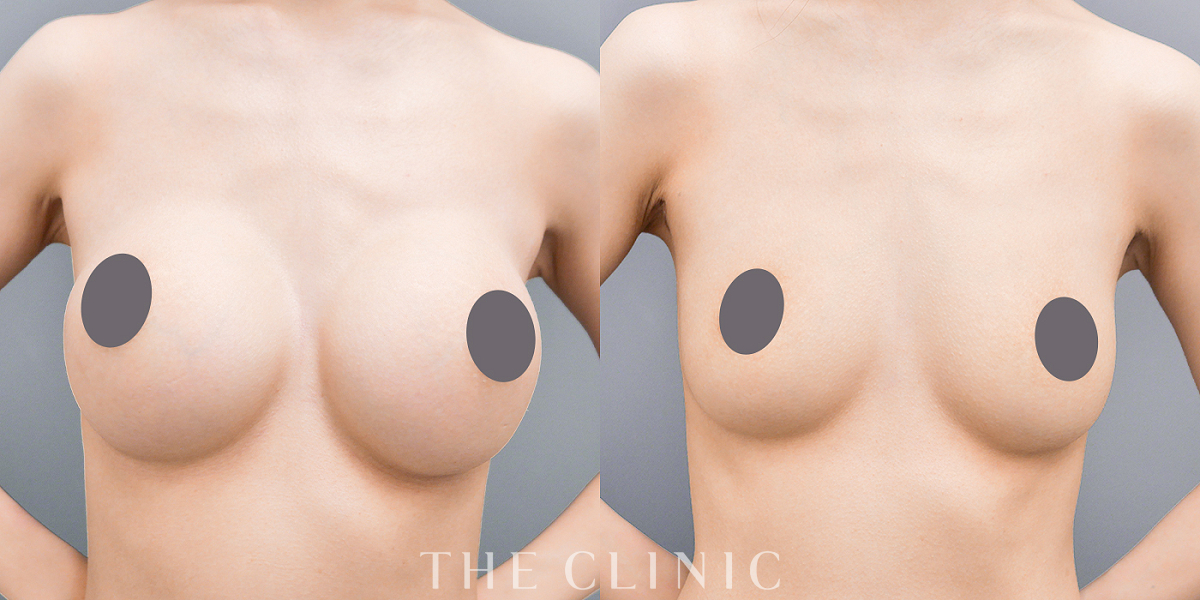

不自然な形のアクアフィリング(アクアリフト)豊胸除去(35歳女性) (35歳女性)

コンデンスリッチ豊胸を行うために、前もってアクアフィリングの除去を行いました。エコーで確認するとかなり厚い被膜が形成されています。

アクアフィリングは生理食塩水で溶解されるとのことで、エコー下に生理食塩水を注入しましたが、なかなか溶解できず、ヒアルロニダーゼも追加してなんとか溶解除去することができました。右側は炎症があった為か、汚く濁った状態でした。

| 概要: | アクアフィリング除去+コンデンスリッチ豊胸:乳腺用エコーを用いて、バスト内の状態を確認。その後、生理食塩水でアクアフィリングを溶解する。溶解仕切れない場合には、注射器で吸い出し除去。アクアフィリング の除去後、バストの皮下にコンデンスリッチファット(老化細胞や不純物を取り除いて濃縮させた自己脂肪)を注入。 |